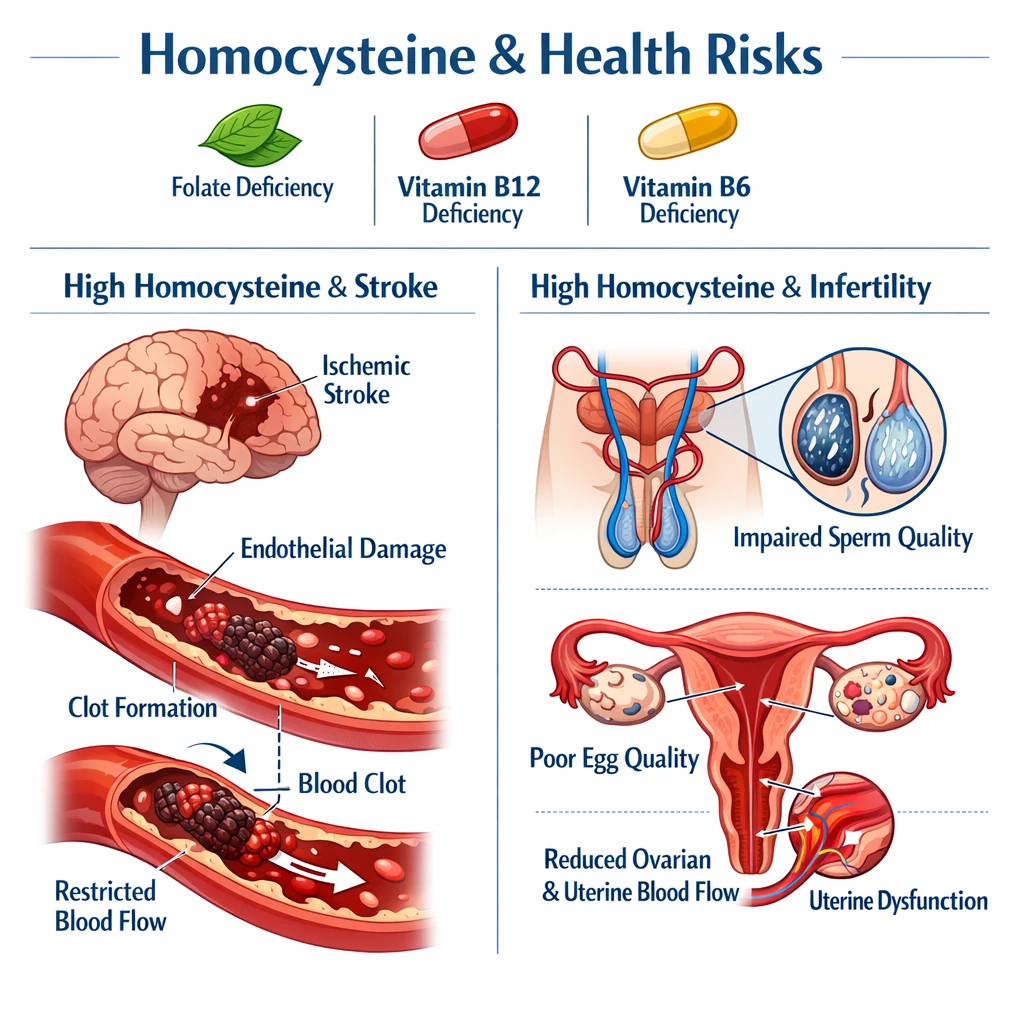

– اختلال در تنظیم کلسیم داخل سلولی: در حضور سموم مانند سرب و جیوه، نبود ویتامین D باعث افزایش ورود کلسیم به سلولهای عصبی و مرگ نورونی میشود.

– کاهش فعالیت گلوتاتیون (GSH): سطح پایین ویتامین D تولید آنتیاکسیدان اصلی مغز را کاهش داده و سلولها را در برابر پراکسیداسیون چربیها آسیبپذیر میکند.

– تقویت التهاب میکروگلیال: کمبود ویتامین D منجر به فعالسازی میکروگلیا و آزادسازی سیتوکاینهای التهابی (IL‑۶، TNF‑α) میشود که اثر سموم را چندبرابر میکند.

– تضعیف سد خونی–مغزی (BBB): بررسیها نشان دادهاند که سطح سرمی ویتامین D کمتر از ۲۰ ng/mL با افزایش نفوذ سموم فلزی به مغز همراه است.

– سرب (Lead): سبب کاهش کلسیتریول در مغز و مهار گیرنده VDR میشود؛ این اثر در افراد دچار کمبود ویتامین D دوچندان است.

– جیوه (Mercury): در غیاب ویتامین D، سمّیت اکسیداتیو آن افزایش یافته و مرگ نورونی در قشر حرکتی بیشتر میشود.

– آلومینیوم و منگنز: کمبود ویتامین D پاسخ التهابی مزمن را تشدید کرده و سبب افزایش فیبروز آستروسیتی در بافت مغز میشود.